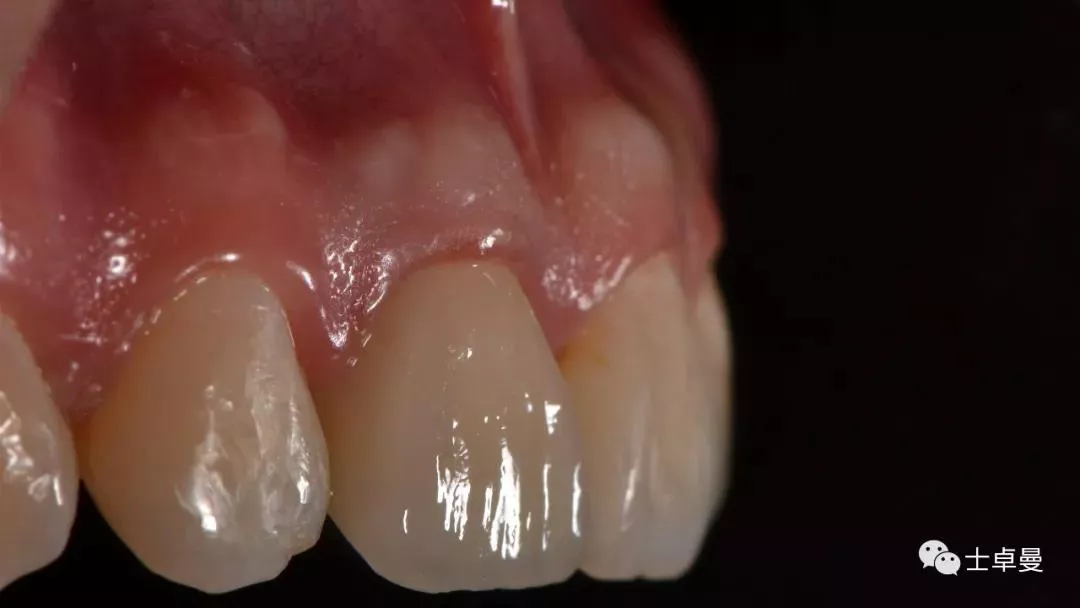

临时修复后2个月,龈缘及龈乳头位置理想,软组织健康

· 2个月后,见唇侧骨弓轮廓可,龈缘及龈乳头形态自然,去11临时修复体,植体ISQ值测定82,个性化取模,试戴Variobase氧化锆基台+LAVA氧化锆单冠,就位被动性良好,增加基台扭力至35Ncm,粘接固位上部冠,调合抛光。